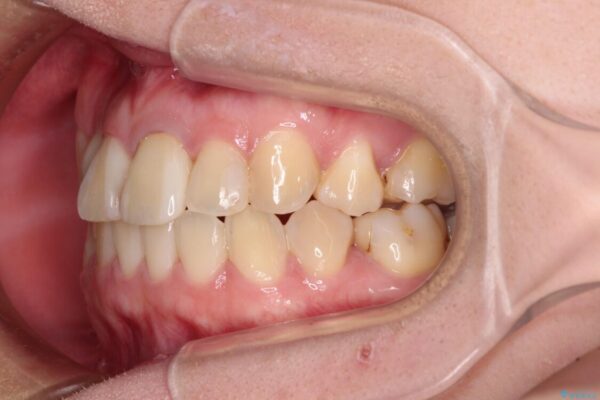

治療途中

• 虫歯治療ついでに歯並びの後戻りを改善 インビザラインによる矯正治療 治療途中画像